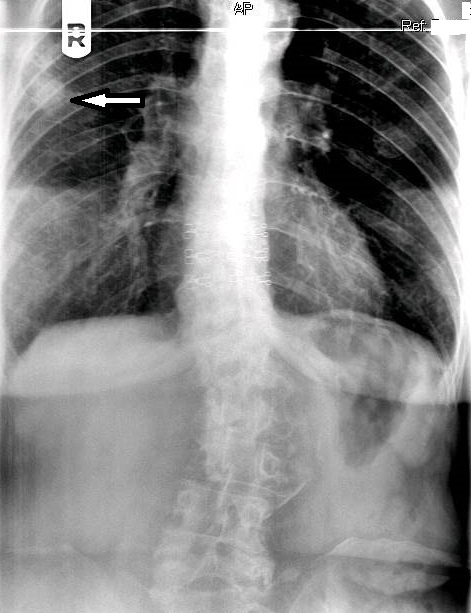

The chest series was obtained and again demonstrated the lesion noted previously on the thoracic spine. The lesion is more clearly seen on figure 3, the PA chest projection.  It measured 3.0 cm in the long axis, and the border was not particularly sharp and appeared somewhat spiculated on close inspection (open arrow points to lesion). No calcifications were noted within the lesion. This finding is worrisome, as benign granulomatous lesions, which are often discovered incidentally, frequently manifest some degree of calcification, while more aggressive lesions exhibit calcification less often. Figure 4 again demonstrates the thoracic spine compression fractures.